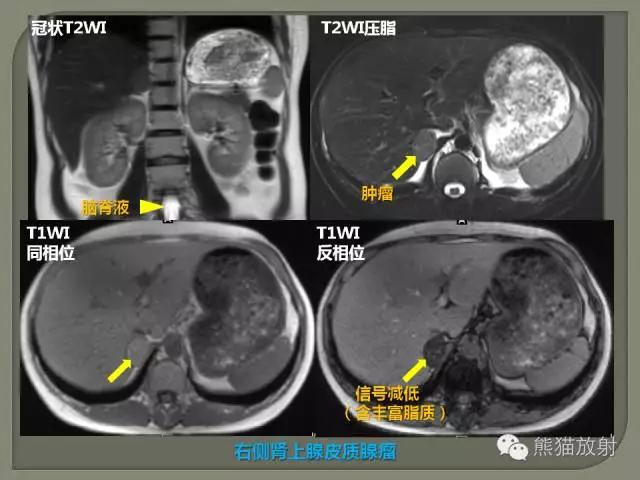

3、水为长T1长T2,脂肪为短T1长T2。

4、长T1为低信号(暗),短T1为高信号(亮)。

5、长T2为高信号(亮),短T2为低信号(暗)。

6、水T1黑,T2白。

7、脂肪T1白,T2灰白。